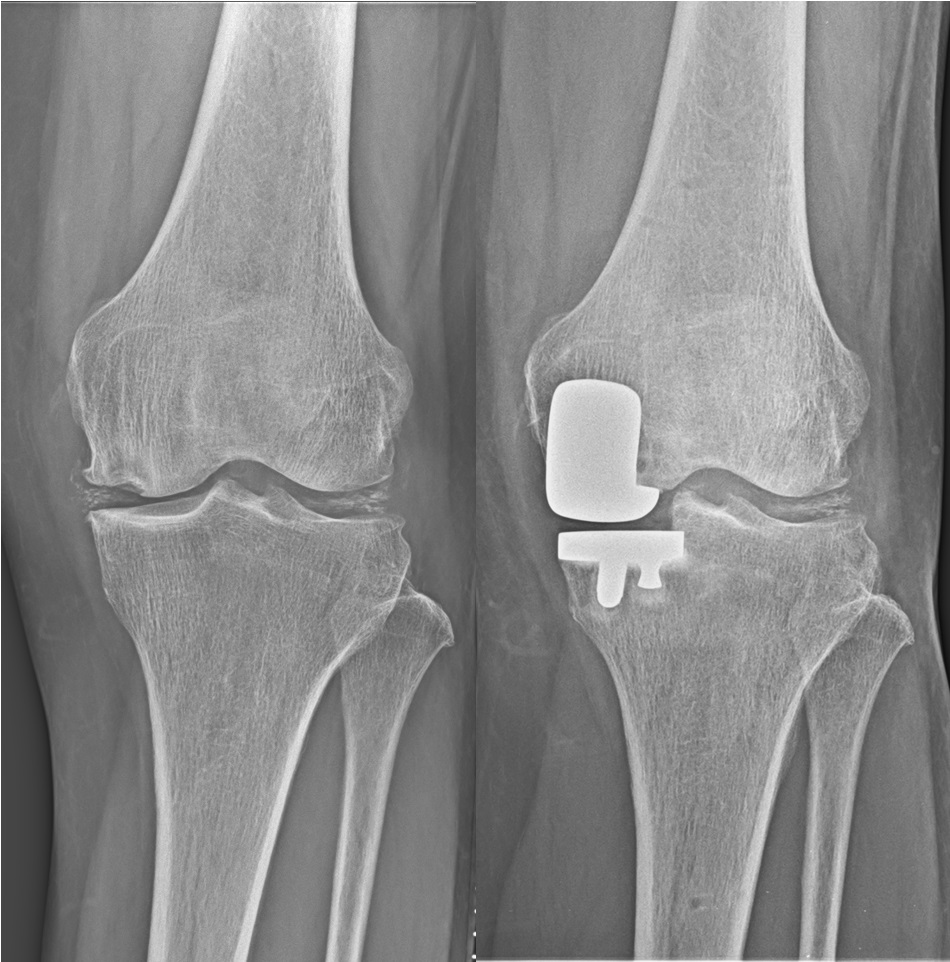

人工膝関節単顆置換術(unicompartmental knee arthroplasty: UKA)

膝関節の内側または外側のみの変形に対して適応があります。

片側のみの人工関節置換術であることから、体への負担が少なく、早期より痛みが改善し歩行が可能となります。

人工膝関節全置換術(total knee arthroplasty: TKA)

末期の変形性膝関節症に対してはTKAを行います。

術前の膝の状態を考慮した上で、それぞれに適切な機種および術式を選択しております。